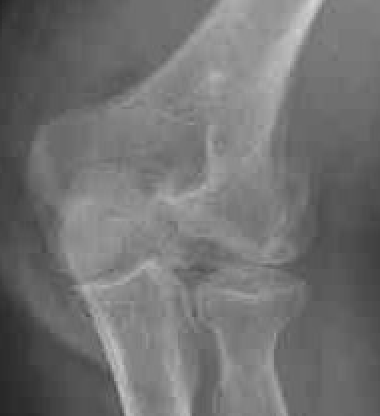

Coronal shear fracture of the distal humerus

Capitellum +/- trochlea

Bryan & Morrey Classification

| Type I | Type II |

|

Large osseous fracture of the capitellum

Articular cartilage injury with little bone |

Hanh Steinthal fracture

Kocher Lorenz fracture |

| ORIF | Typically remove |